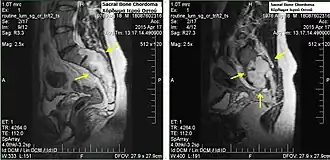

Sacral bone chordoma

Chordomas can arise from bone in the skull base and anywhere along the spine. The two most common locations are cranially at the clivus and in the sacrum at the bottom of the spine.[2] Very rarely, chordomas present outside of the skull base or spine; these are called extra axial chordomas.[3]

Sacral chordomas make up 2 to 4% of all primary bone tumours and 44% of all primary sacral tumours, thus making it the most common malignant sacral tumor. About 50 to 60% of chordomas are located in the sacrococcygeal region. Males aged between 40 and 50 years are twice as likely as women to get sacral chordoma.[28]